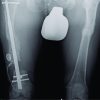

A 6 year-old male child presented with bilateral gradually progressive genu varum deformity of 4 years’ duration (Fig. 1).

There was no significant past medical and family history which is rare for autosomal recessive inheritance. Birth history was normal term vaginal delivery with the normal physical measurement at birth. On general examination, weight was 11 kg (<3 SD), short stature (70 cm), mentally sluggish, pigeon-shaped chest, and exaggerated lumbar lordosis. Neurological examination was normal. There was no clinical sign of rickets and blood investigation for bone profile was normal. Quantitative estimation and 2D electrophoresis of glycosaminoglycan in urine were done to rule out mucopolysacridosis. A plain radiograph of his knee, pelvis, and spine shows some classical signs of skeletal dysplasia (Fig. 2). Gene testing was done to confirm a diagnosis.

Clinical manifestations of DMC include pigeon-shaped chest, increased lumbar lordosis, broadening of the metaphysis, and brachydactyly [5]. Short neck with elevated shoulder joints, shortening of the upper extremity, and genu valgum or varum (Fig. 2b) were also present in most cases described in the literature. Rare manifestations include kyphoscoliosis, limitation of extension of joints, clinodactyly and camptodactyly of the fingers, prominent heels, flat feet or talipes equinovarus, bowing of femur, and tibia. Mild to severe mental retardation is present in all cases. The patients may also have delayed bone age, microcephaly, protruding abdomen, and generalized hirsutism. Tone, reflexes, and external genitalia are usually normal in DMC. The radiological findings include microcephaly with facial bone dysmorphism, small irregular epiphysis with often delayed ossification seen most commonly in proximal humerus and femur, and irregular metaphysis [6]. A plain radiograph of the pelvis with both hips shows a classical semilunar, irregular lacy appearance around the iliac crest which is a pathognomonic radiological sign of this syndrome (Fig. 2c) [7,8]. The lacy appearance is due to bone deposition in a wavy pattern which appears at around 3–4 years of age and persists up to adulthood. There is an asymmetric bilateral widening of the sacroiliac joint. A radiograph of the dorsolumbar spine shows platyspondyly and central depression of vertebral bodies’ endplates (Fig. 2a). These double-hump-shaped endplates with the constricted central part are also characteristic of DMC syndrome. Other features are small or short ischium, hypoplastic acetabulum, hypoplastic femoral head and neck, medial beaking of the femoral neck, delayed pubic ramus synchondrosis, wide pubic symphysis, and bilateral dislocation of hip joints, odontoid hypoplasia, and atlantoaxial instability. The radiographic lacy appearance of iliac crests and generalized platyspondyly with double-humped end plates are pathognomonic of DMC and thus act as an easy pointer to diagnosis eliminating 435 genetic skeletal dysplasia’s, directing appropriate genetic workup and counselling [9]. The closest differential diagnosis is Morquio’s disease, but absent clouding of the cornea, valvular disease, organomegaly, and the presence of typical radiology support DMC. Joint stiffness is present in DMC, unlike the hyperlaxity seen in Morquio disease. The prognosis is better in DMC related to Morquio disease. We planned the patient for guided growth with eight plates but the patient lost to follow up due to coronavirus disease 2019 [10].